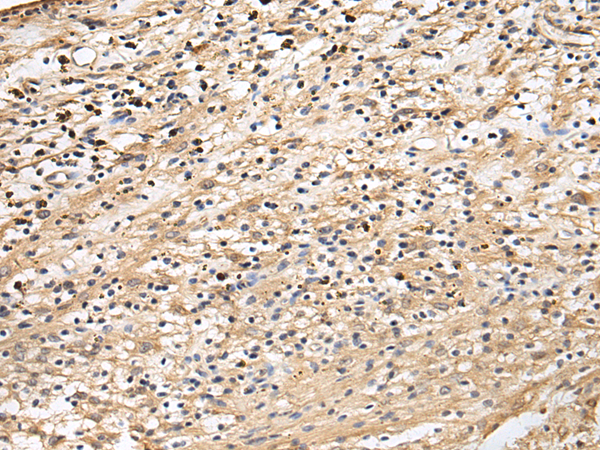

IHC positive control: |

Human brain |